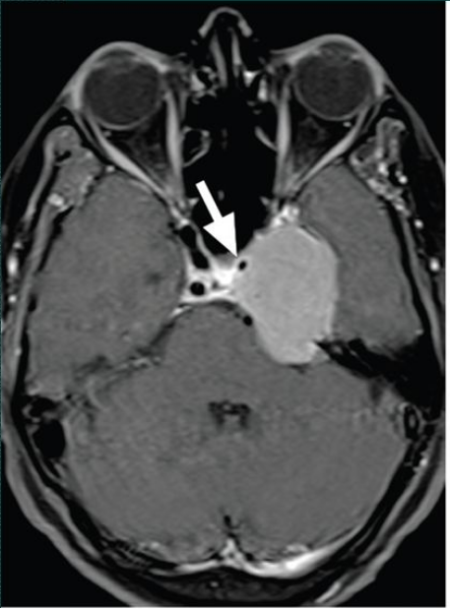

圖:海綿竇區(qū)頸內(nèi)動(dòng)脈瘤